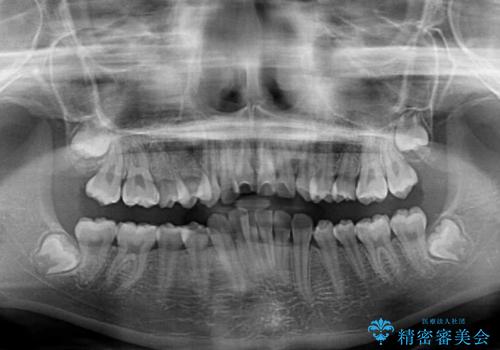

- 前歯の叢生と深い咬み合わせを気にして来院された患者様です。

奥歯の咬み合わせを見ると、上顎が下顎に対して相対的に前方にありました。

深い咬み合わせを改善するためには、上顎臼歯を後方に移動させつつ、下顎の小臼歯を直立させる必要があります。

インビザライン単体で対応ることも検討できますが、達成する可能性が低いため、カリエールディスタライザーという補助装置を併用して、より確実性を上げることとしました。

奥歯の咬み合わせと深い咬み合わせを改善した後、インビザラインで歯列を整えることとしました。

ワイヤー装置と補助装置を有効に活用し、さらには高校生ということもあり、1年9か月で狙い通りの仕上がりを達成することができました。